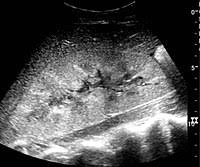

Acute and chronic renal failure are the two kinds of kidney failure. It means that your kidneys have abruptly stopped working, usually within the course of two days. Might they be a contributing factor to the. Chronic renal failure, or chronic kidney disease (ckd), is a slow and progressive decline of kidney function. Kidney biopsy (renal biopsy) is a procedure where the doctor pushes a thin needle through your skin and takes a small piece of your kidney to look at under a microscope. They are responsible for the removal of waste products from the body, the regulation of body fluids and the production of some hormones. Renal failure patients also have deficiencies in coagulation factors that may raise the tendency of bleeding. It's usually a result of a complication from another serious medical condition such as diabetes, high blood pressure or cardiovascular disease.